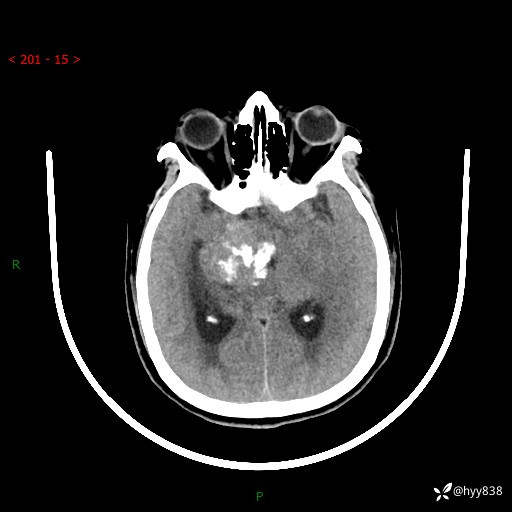

颅脑CT平扫